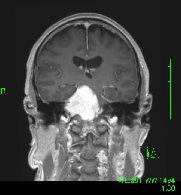

症例2) 31歳女性、頭蓋底部巨大髄膜腫、外科手術+放射線治療

<画像所見>

腫瘍はほとんど消失している。術後患者様は右眼瞼下垂、複視(動眼神経麻痺)生じたが、自宅退院された。